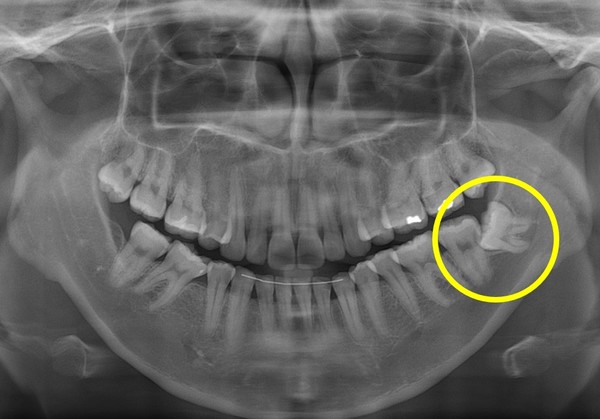

사랑니는 사랑을 하게 되면 그 존재감을 들어낸다는 속설이 있습니다. 저의 경우 6개월에 1번씩 검진을 받고 있는데 어느 날 담당 주치의 선생님께서 이제 사랑니를 뽑을 때가 되었다고 하셔서 당일 아무런 준비도 없이 그냥 사랑니와 매복 사랑니를 하나씩 뽑았습니다. 지금 생각해 보면 남은 1개마저 뽑을껄 무서움에 2개만 뽑은 게 후회가 됩니다. 2개를 뽑는다고 해서 고통이 2배인 것은 아니었으니 3개를 뽑아도 고통은 똑같았을 것 같습니다. 턱 주변이 붓고 얼굴이 이상하게 붓고 열감과 가끔 오는 통증 때문에 휴식도 마음 편하게 취하지 못했습니다.

치과 치료를 하면 알 수 있는 것이 치아는 함부로 뽑지 않습니다. 정말 최대한 살려보고 그래도 안 되면 뽑아서 임플란트 등으로 빈자리를 채웁니다. 사랑니는 다른 치아들과 달리 발치를 해야 할 때도 있습니다. 잘 자란 사랑니는 특별한 문제를 일으키지 않아 뽑지 않아도 됩니다. 하지만 대부분의 사랑니는 말썽을 부립니다. 출혈, 염증, 통증 및 악취, 충치 들 여러 가지 문제를 일으킬 확률이 높기 때문에 뽑아야 합니다.